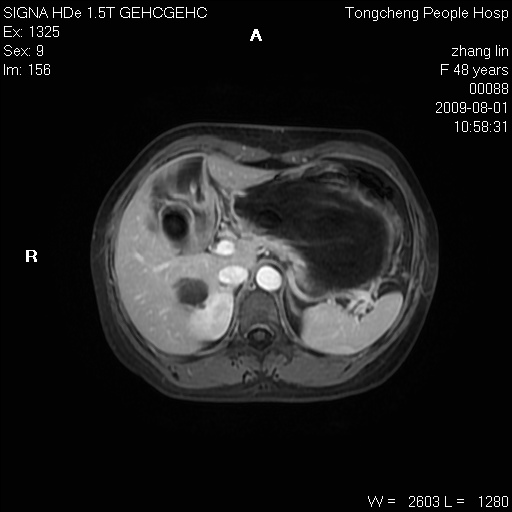

女,48岁。健康体检,彩超发现右肾占位性病变。平素健康。

临床诊断:右肾占位性病变,性质待定(囊肿?肿瘤?)。

上中腹部mr平扫+增强扫描,图像如下:

右肾上极见一类圆形病灶,t1wi呈等信号t2wi呈等高混杂信号,三期增强无强化,边界清---考虑囊肿出血。

同反相位均表现为等信号,病变无强化,考虑含蛋白的囊肿可能,弥散加权相或许有些帮助,